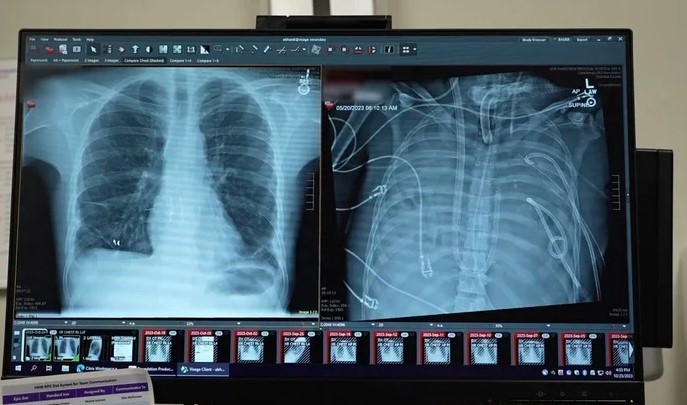

Эрхтэн шилжүүлэх мэс засалд хувьсгал гаргасан нэгэн эмнэлзүйн туршилтын талаар анагаах ухааны “Med” сэтгүүлд мэдээлжээ. Тодруулбал, уушгины хүнд өвчтэй нэгэн эрэгтэйн хоёр уушгийг бүрэн авсны дараа уг өвчтнийг хиймэл уушгины аппаратаар 48 цагийн турш амьд байлгаж, эмч нарт эрхтэн шилжүүлэн суулгах хугацаа өгсөн байна.

2023 оны хавар АНУ-ын Нортвестернийн их сургуулийн Мемориал эмнэлэгт амьсгалын хурц дутагдалын хам шинжээр оношлогдсон 33 настай эрэгтэй хандсан байна. Тэрбээр үхжил үүсгэдэг уушгины хатгалгаа, хүнд хэлбэрийн сепсистэй болсон байсан бөгөөд хиймэл амьсгалын аппаратад залгасан боловч биеийн байдал нь улам дордож, эхлээд бөөрний дутагдал, дараа нь зүрхний үйл ажиллагаа нь доголджээ.

Ингээд Чикагогийн Умард – Баруун их сургуулийн Файнбергийн Анагаах ухааны сургуулийн цээжний хөндийн мэс заслын эмч Анкит Бхаратагийн удирдсан эмч нарын баг өвчтөнд халдварын улмаас гэмтсэн уушгийг авах, хиймэл уушгины шинэ системээр амьдралыг нь дэмжих онцгой шийдвэр гаргасан байна.

48 цагийн дараа уг өвчтөний байдал сайжирч эхэлжээ. Бхаратагийн хэлснээр, бөөрний үйл ажиллагаа бүрэн сэргэж, зүрх хэвийн ажиллаж эхэлснээр даралт дэмжих хэрэгсэл шаардлагагүй болсон байна. Дараа нь түүнд хоёр уушгийг амжилттай шилжүүлэн суулгасан бөгөөд гадны эрхтнийг хүлээж авахгүй байх, эсвэл эрхтний үйл ажиллагаа алдагдах шинж тэмдгүүд илрэхгүй байгаа аж.